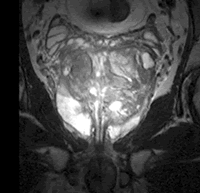

近日,Medrad公司的直肠内线圈(3.0T Prostate eCoil)获准在美国上市,该设备可与通用(GE)Signa HDx 3.0T磁共振扫描仪合用,对前列腺及其周边组织进行高解析度磁共振成像和波谱检查。据介绍,该设备的球囊与前列腺大小和外形匹配,因此腺体和线圈信号扩增单元之间可连贯接触,从而保证小视野内的高空间解析度、敏感性和特异性。该设备能对前列腺癌特异性胆碱峰更好地定量分析,有利于早期诊断并优化治疗方案。此前,FDA已经批准了该设备系列中的1.5T磁共振用线圈。, http://www.100md.com